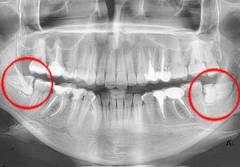

Зубы мудрости, или третьи моляры, прорезываются в возрасте 12-26 лет на нижней челюсти и 17-22 года на верхней. Этот процесс может протекать без симптомов, но часто сопровождается болью и ухудшением общего состояния.

- Недостаток места для зуба — основная причина боли. Челюсть уже сформирована, и зубу приходится преодолевать препятствия, что вызывает воспаление.

- Неправильный рост зуба. Зубы мудрости могут расти в неправильном направлении, что вызывает боль и может повредить соседние зубы.

Некоторые стоматологи рекомендуют удалять зубы мудрости, если они не имеют функционального значения. Удаление следует проводить только при наличии показаний, таких как неправильное положение зуба или воспаление.

Третьи моляры, или зубы мудрости, прорезываются в возрасте 12–26 лет на нижней челюсти и 17–22 лет на верхней. Этот процесс может быть безсимптомным, но часто вызывает дискомфорт в деснах и общее ухудшение самочувствия.

- Недостаток пространства для прорезывания зуба. К моменту появления зуба мудрости челюсть уже сформирована, и зубу приходится преодолевать препятствия, что может вызвать механическое повреждение десны и воспаление.

- Неправильный рост зуба. Зубы мудрости могут расти в неправильном направлении — к щеке, языку или соседним молярам, вызывая болевые ощущения. Горизонтальный рост может разрушать соседние зубы и деформировать зубной ряд, приводя к подвижности зубов и инфекциям. Неправильный рост может сдавливать нерв, вызывая онемение челюсти, особенно при нижних третьих молярах.

Некоторые стоматологи советуют удалять все третьи моляры, так как они не имеют особого функционального значения. Однако удаление следует проводить только при наличии показаний, таких как неправильное положение зуба, негативное влияние на соседние зубы и воспалительный процесс.